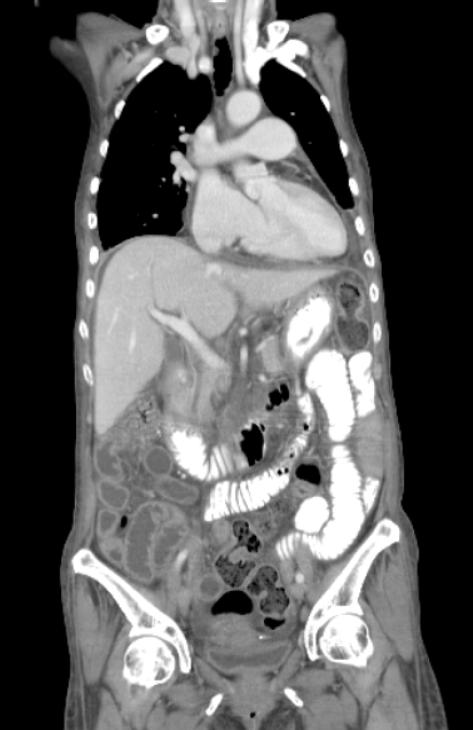

食管胃十二指肠镜和结肠镜检查未见明显病变;腹部CT显示小肠壁增厚,腹中存在大量积液,淋巴结肿大,肠系膜脂肪密度增高(图A),且骨髓穿刺无异常发现。因此,患者来我院求进一步诊治。

图A